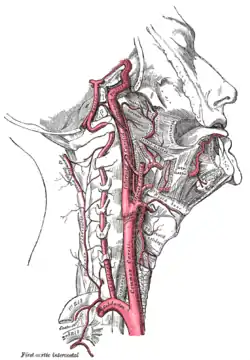

Carotid artery dissection is a separation of the layers of the artery wall in the carotid arteries supplying oxygen-bearing blood to the head. It is the most common cause of stroke in younger adults.[1]The term 'cervical artery dissection should also be considered in the context of this article.[2]

The carotid arteries are a pair of large bore arteries in the neck, they further divide into smaller vessels, the external and internal carotids on both the right and left side of the head/neck.[3] Carotid arterial dissections occur when a tear or rip in the layers of the carotid arterial wall allows blood to flow between the layers of the artery. Artery dissection is not unique to the carotid artery system and can happen in numerous arteries in the body.